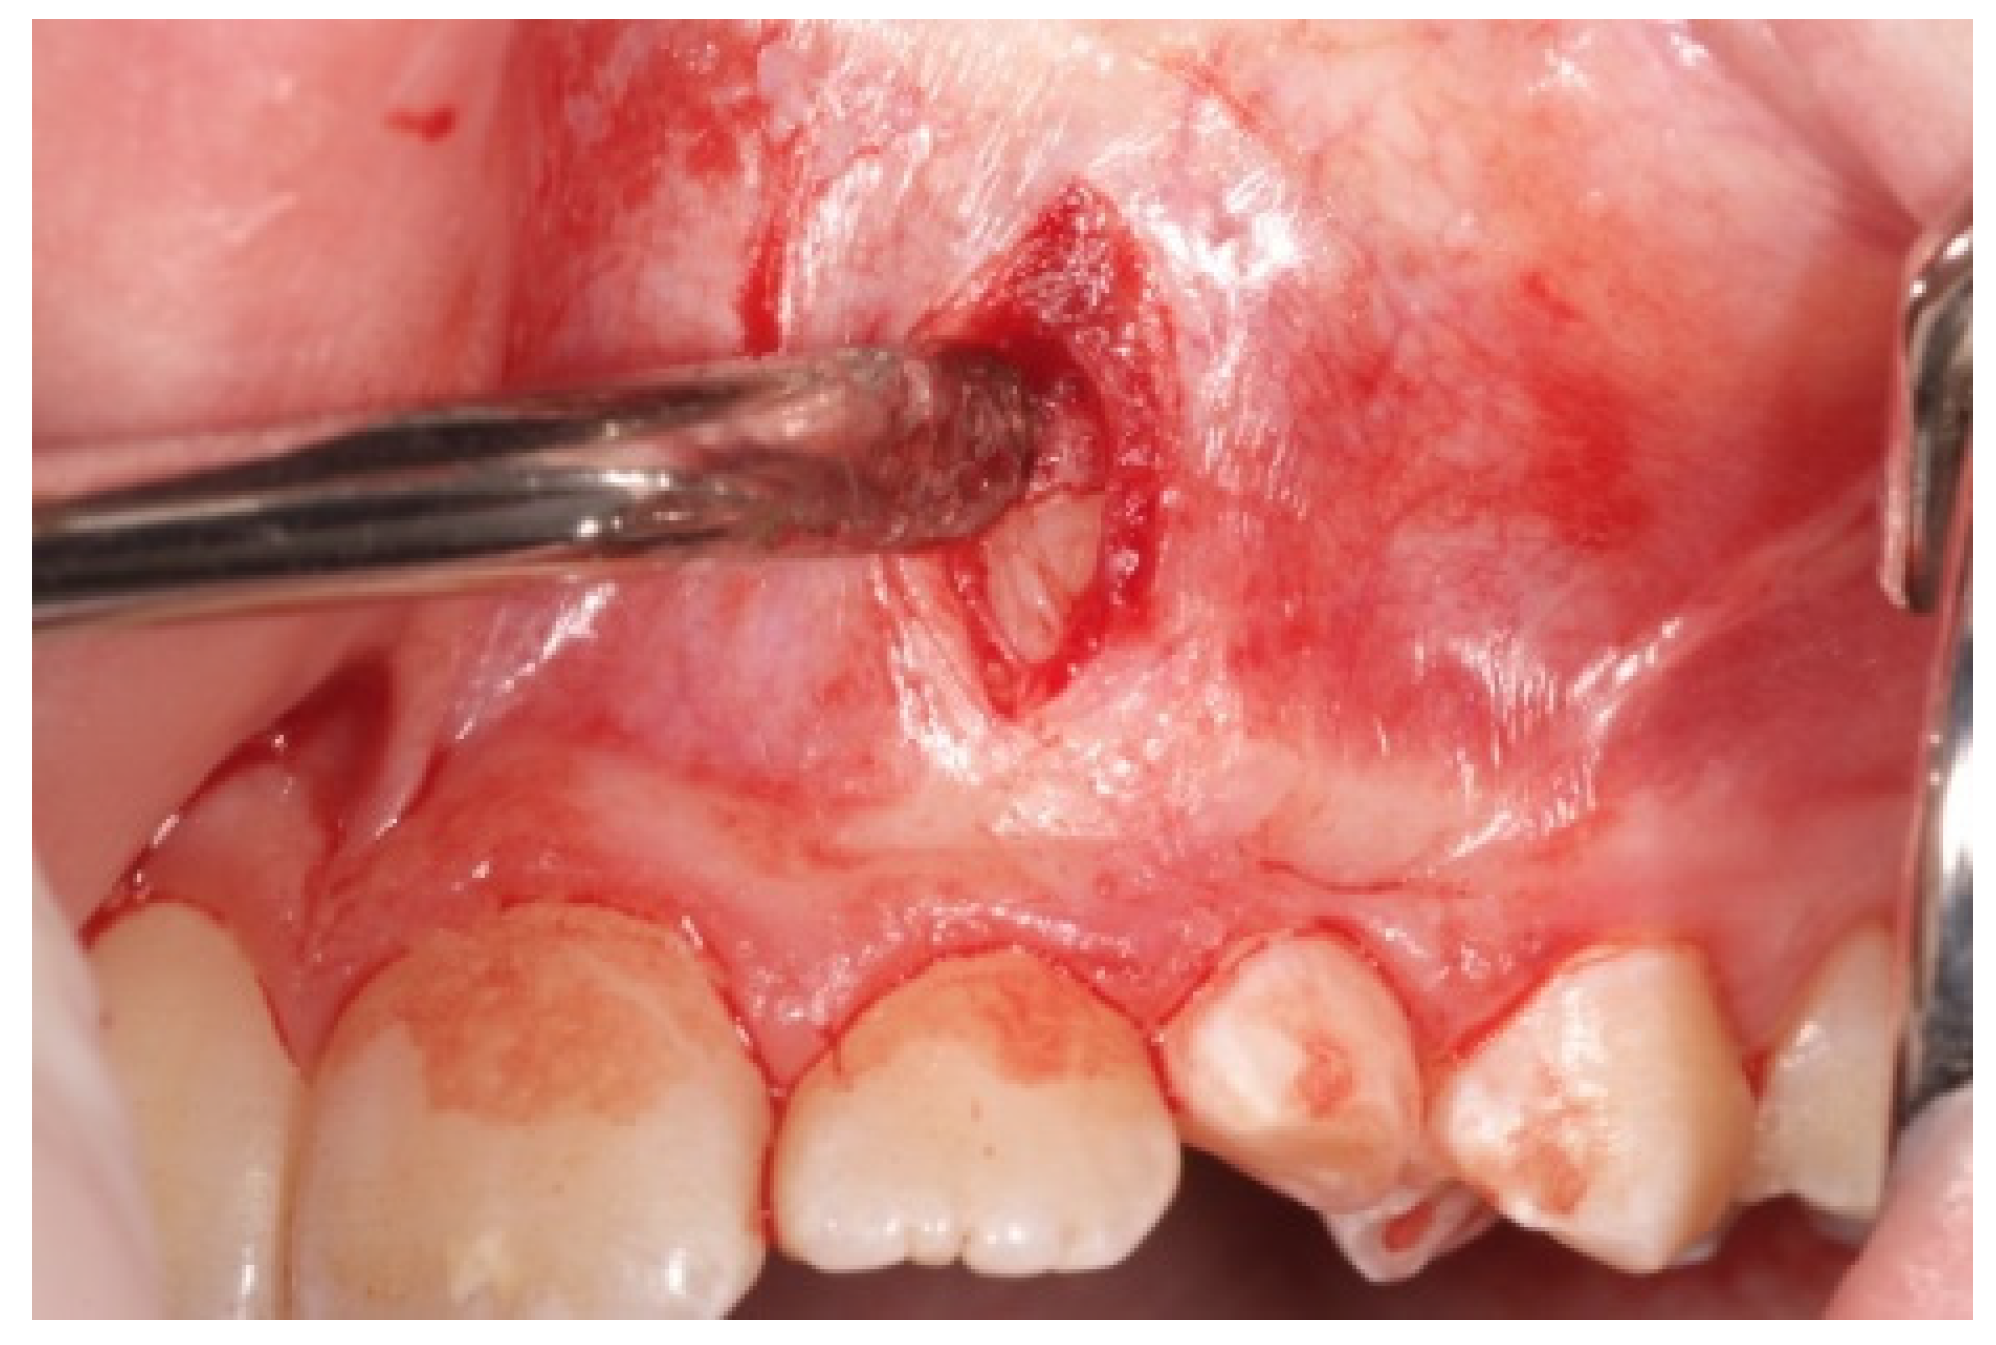

- A first vertical incision, at the level of the impacted tooth crown, and its exposure, with a periosteal elevator, are then performed. If a bony cortex is present overlying the crown, a small bony cavity is made using the multi-blade conical burr with a low-speed right-angle handpiece to expose all of the canine’s crown surface (Figure 3). In any case, a thin groove must be present peripherally to the canine’s crown to guarantee a good isolation from bleeding. Moreover, a further ostectomy is performed on the tooth side toward which the orthodontic traction will be performed (traction route);

- A second vertical incision is made between the first and second premolar, and the sub-periosteal tunnel is created with a periosteal elevator to connect the two incisions from front to back (Figure 4);

- After a good hemostasis is reached, the button is attached to the buccal canine crown’s surface, following all necessary steps including enamel etching with 37% orthophosphoric acid for 30 s and applying adhesive. Therefore, the button is connected by means of a metal ligature to a 150 gr closed coil spring (NiTi). At the distal end of the NiTi coil, another metal ligature is inserted to facilitate the passage of the traction system under the subperiosteal tunnel (Figure 5);